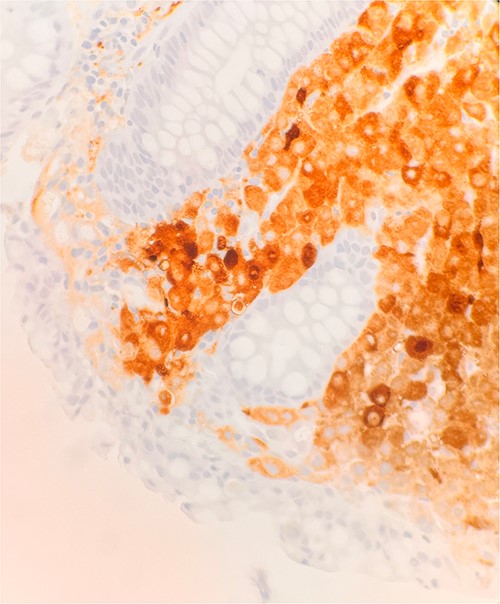

Immunohistochemical stains demonstrate the tumor cells to be strongly positive for vimentin, pankeratin, CK7, CK20, chromogranin, synaptophysin, CD45, and focally positive for CD56. Additionally, there were strongly and diffusely positive findings for S100 (Fig. 3), SOX10, and PRAME. Ki67 shows increased proliferative activity at estimated 25–30%. CD99 shows weak and patchy membranous staining while CK-PAN, p63, desmin, and smooth muscle actin are negative. The described morphology and immunoprofile are consistent with malignant melanoma.

Microscopic examination reveals sheets of round are positive for S100. IHC stain 40×.